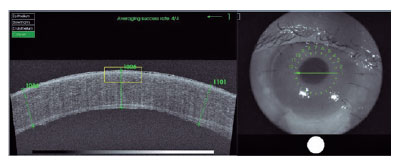

At the four-month follow-up, the patient continued to have no complaints. However, biomicroscopy and OCT (Figure 3) showed worsening of the corneal edema, epithelial microcysts, and reactive miosis. Scleral thinning was maintained. Eye closure was preserved, with no scleral show. The BDT and BVCA measurements were maintained. A triple procedure for ocular rehabilitation was indicated but the patient declined.